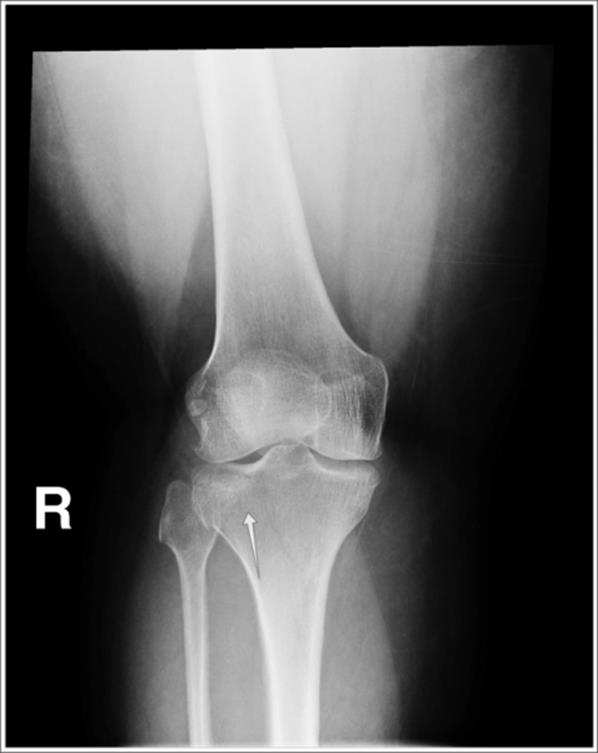

· On plain films, tibial plateau fractures can be radiographically occult; radiographically subtle; or clearly seen (Figure 4.9, Figure 4.10, Figure 4.11, Figure 4.12)

Figure 4.10 A larger, slightly depressed lateral tibial plateau fracture fragment (arrow). (Image courtesy of Arun Sayal, MD.)